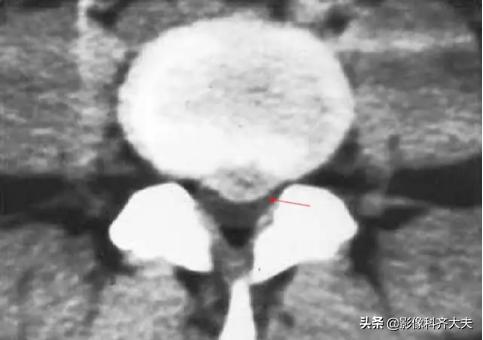

CT显示椎间盘突出(中央型)